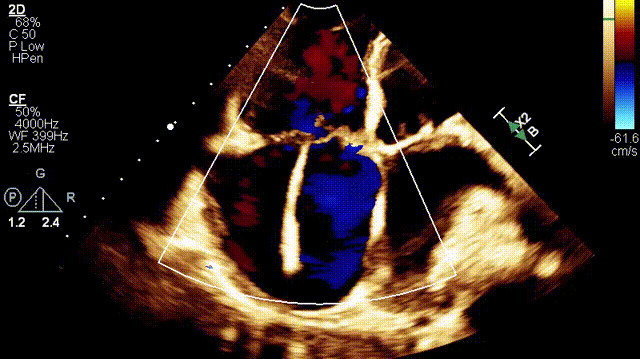

植入前超聲

手術在全麻狀態下開展,此次手術采用經右側頸靜脈入路的方式將輸送器送入患者心臟內,在TEE及DSA引導下調整輸送器頭端角度,使得輸送器與三尖瓣瓣環平面垂直。在輸送器進入右心室后釋放室間隔錨定裝置,而后釋放瓣葉夾持件(2個耳片結構)成垂直狀態。在TEE及DSA確定夾持件固定至三尖瓣葉根部且位于右室側后釋放人工瓣心房側盤片。隨后調整瓣膜同軸性以及室間隔錨定件位置(貼合室間隔),前推藏針管并固定,進而釋放室間隔錨定裝置,并再次確認瓣膜位置、穩定性及同軸性,合攏輸送鞘后撤出輸送器,完成LuX-Valve Plus人工三尖瓣瓣膜的植入。